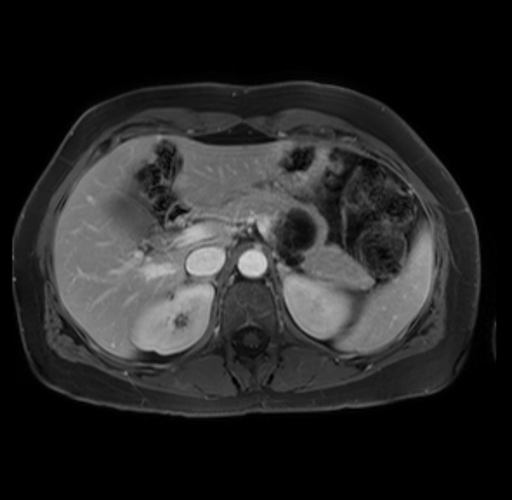

Imaging Analysis

Look through the patient's CT scan to identify any areas of concern for the necessary procedure.

Based on your CT findings, which issue(s) are present and would give reason for "planned slowing down moment(s)" in this case?

Considering a standard distal pancreatectomy procedure, what step(s) of the operation would you do differently in this case?